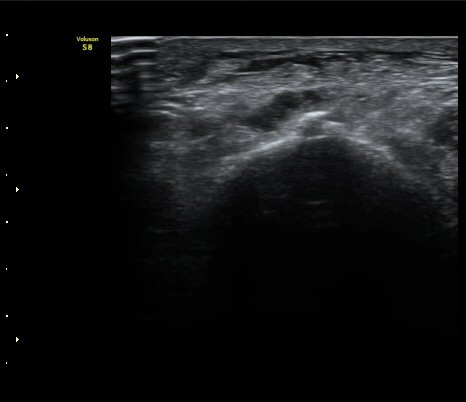

Á¾°ñÀÔ¹æ°ñÀÎ´ë ¿ÜÃø Á¾´Ü¸é°Ë»ç¿¡¼­ ¼ö¾×Àú·ù°¡ °üÂûµÊ(»çÁø 6, 7).